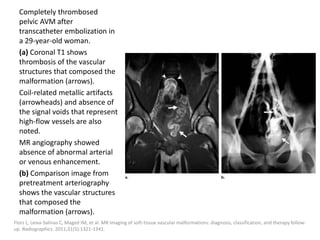

Endovenous ablation techniques

Endovenous ablation techniques like endovenous

laser ablation (ELVA) or endovenous

radiofrequency ablation (ERFA) were successfully

used to close large embryonic venous channels

such as the lateral marginal vein in patients with

Klippel-Trenaunay syndrome (KTS).